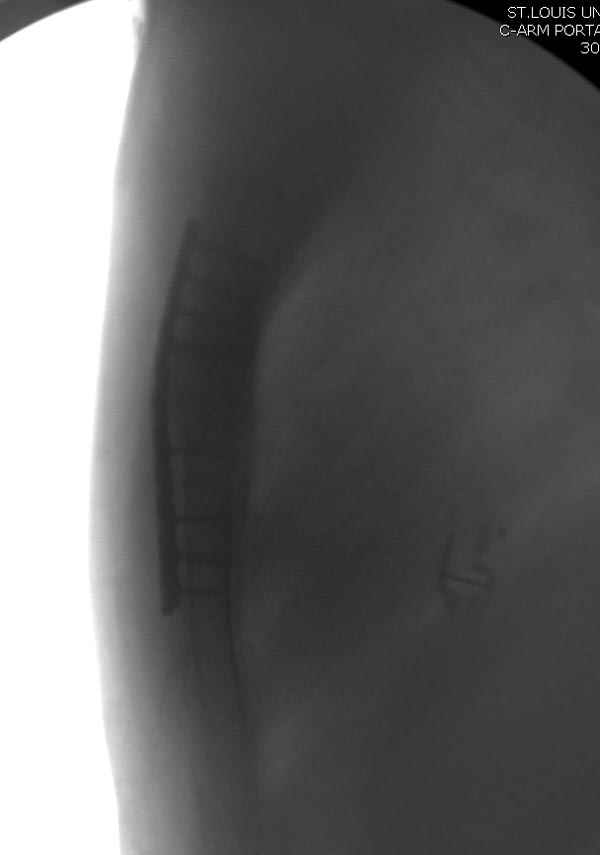

Рентген снимки во время операции и последние сделаны на днях.

При переломах грудины со смещением как правило оперируем. В качестве фиксатора используем рекон. LCP, доступ простой, с репозицией проблем не возникало. Для сверла, что бы не провалиться в средостение, используем ограничитель.

1.jpg